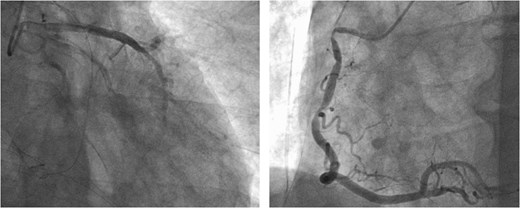

A 73-year-old male presented to his primary hospital with complaints of chest pain. Examination revealed a coronary artery-pulmonary artery fistula and 75% stenosis of the RCA (Figs 1 and 2) with a resting full-cycle ratio (RFR) of 1.0. However, myocardial scintigraphy was negative for ischemia and electrocardiogram (CAG) at rest showed no ST changes (Fig. 3). An exercise resting electrocardiogram (ECG) showed diffuse ST depression, raising suspicion of ischemia due to coronary steal (Fig. 4). Consequently, the patient was referred to our department.

Preoperative CAG showing coronary artery-pulmonary artery fistula and 75% stenosis of the right coronary artery.